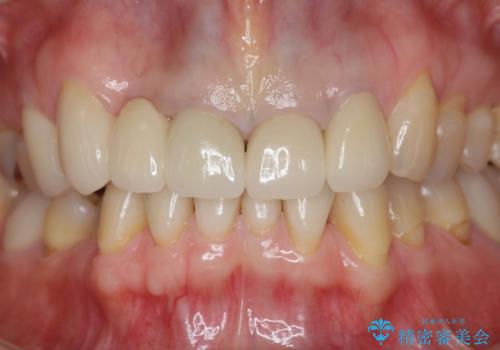

- 66万円(ジルコニアクラウン×5・仮歯×5)費用は治療当時の料金となります

自然な歯の色調や仕上がりに大変満足いただけました。